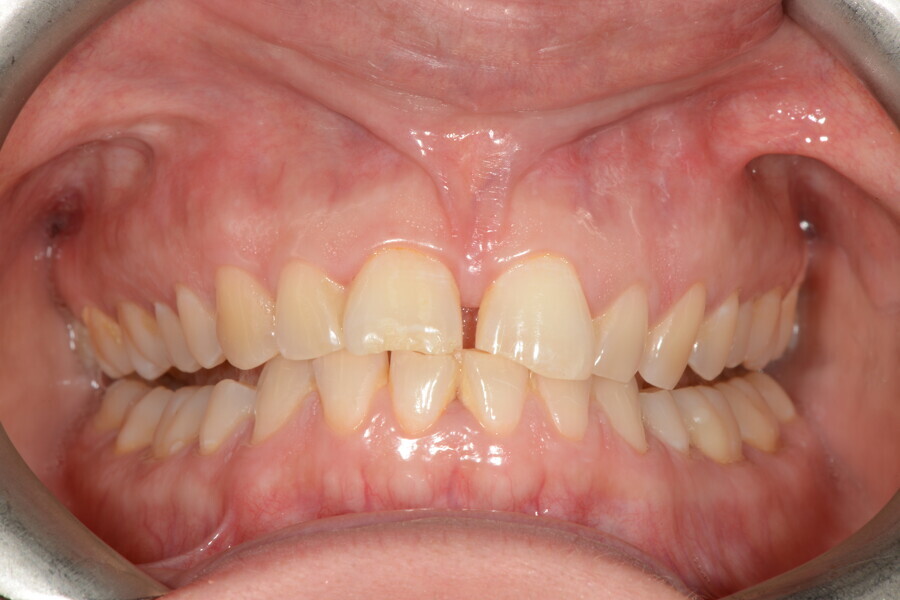

The 58-year-old patient wished to improve his oral aesthetics and function, complaining of mobility of the posterior teeth and wear of the anterior teeth. After data collection, a very complex situation was identified (Figs. 11–13):

1. severe periodontitis with poor prognosis of some teeth;

2. anterior crossbite;

3. severe wear mainly of the anterior teeth and compensatory eruption;38

4. atypical swallowing and lower posture of the tongue at rest;

5. masticatory dysfunction during the mastication test; and

6. no significant signs of temporomandibular disorder.

During the first visit, we checked the centric relation with cotton rolls, eliminating the posterior mesialising precontact and then performed a direct composite aesthetic and functional mock-up in this new position, not only to motivate the patient regarding the final result but also to help him understand better overall why tongue therapy, tooth alignment and dental resurfacing for augmentation of the vertical dimension of occlusion were required (Figs. 14 & 15).